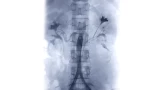

Spinal Vascular Malformation Embolization

Spinal vascular malformations are typically diagnosed on an MRI scan, then further defined by a catheter angiogram.

As mentioned above, SVMs, while rare lesions are very heterogeneous in terms of their location, architecture, blood supply, and symptoms. The two main treatment modalities are endovascular or surgical. For an endovascular procedure, very careful spinal angiography is necessary to define what vessels are supplying the malformation and what vessels are supplying to the normal spinal cord. If this is adequately delineated, embolization may be performed with glue (NBCA) or a glue-like material (Onyx) to block off the abnormal connection. If this cannot be performed safely from a catheter approach due to the blood supply, open surgery may be necessary to place a clip on the abnormal communication without placing other blood vessels or the spinal cord at risk. Each case demands very specific tailoring of a multidisciplinary treatment plan.